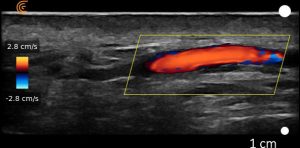

We have been working blindly for many years. And now we can confidently train you to be able to fully map out the face in terms of arteries and much more. We can measure depths of arteries and diameters and much much more.

Our course is a fully comprehensive course that not only provides you with the only ultra high frequency portable ultrasound in the world but also teaches you exactly how to use it to its best effectiveness. Over this two day course. You will cover off complications to the very highest level. Along with the most in depth anatomy training available anywhere.